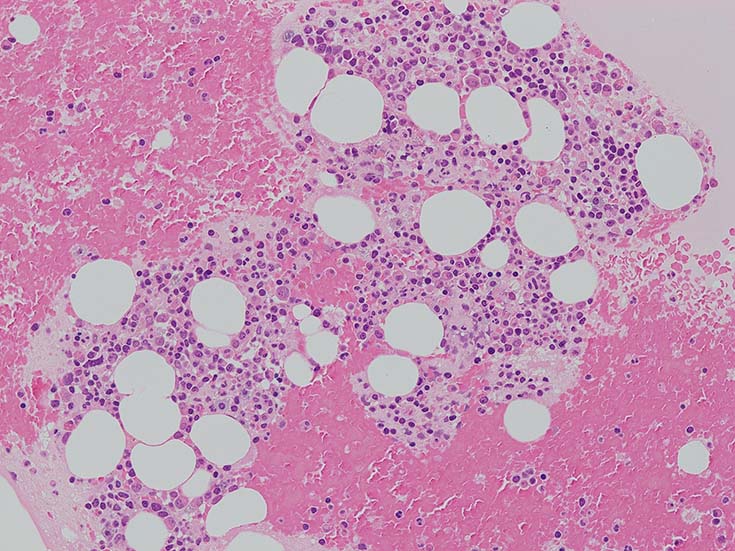

lymphoplasmacytic lymphoma(LPL)

この症例では骨髄組織での造血巣内にリンパ球や形質細胞の軽度増加があるようだが, 腫瘍細胞増殖が明瞭ではない. 結節形成はみられない. mast cellsの増加がNaphtol-ASD-CAE染色で確認される.